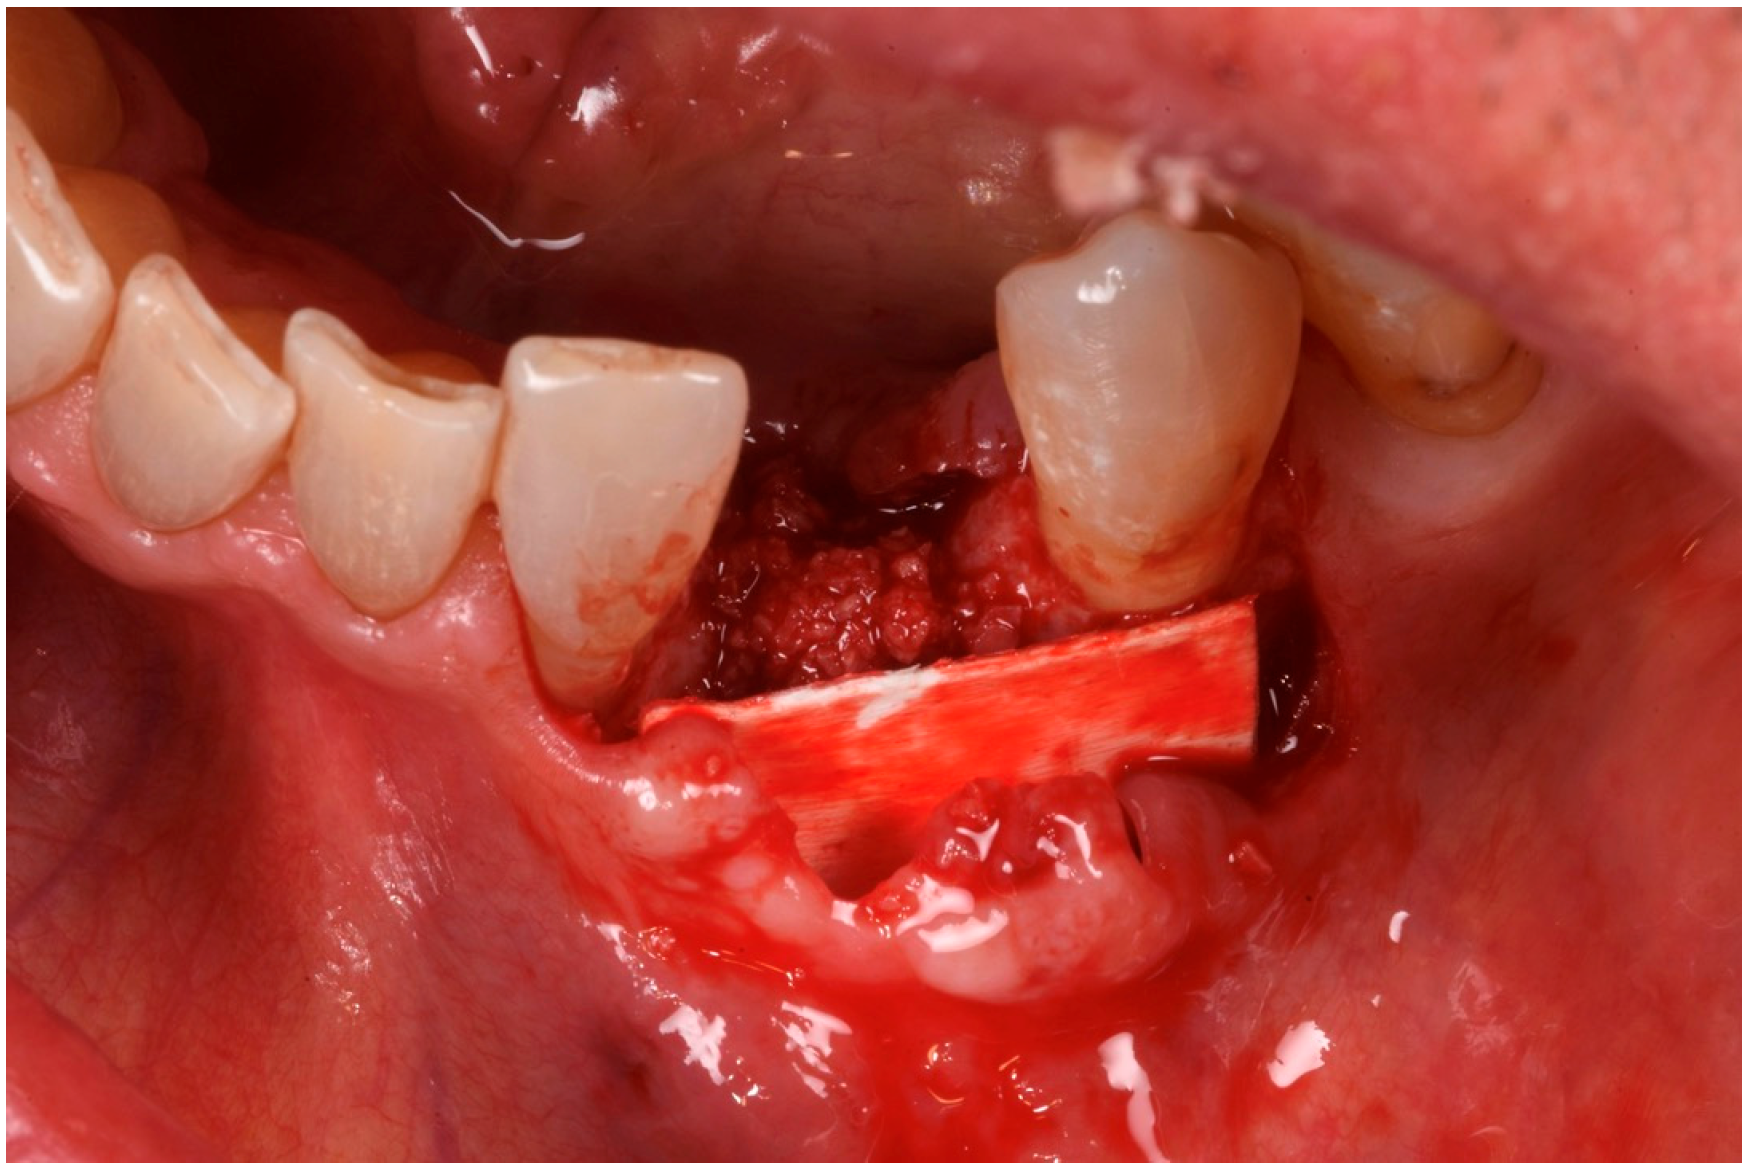

3.2. Hard Tissue Augmentation

The patient was anesthetized with articaine 1:200,000. A flap was designed to extend from the distal aspect of the lateral incisor to the distal of the first bicuspid. In this case, only one releasing incision was made distal to the bicuspid to provide greater flexibility at the mesial aspect, where bone loss was more advanced. A full-thickness buccal and lingual flap was elevated to expose the 3D lesion. The mesial–distal component of the defect measured 13 mm, with a significant portion of the buccal plate completely missing (Figure 4). The vertical component of the defect comprised 9 mm of suprabony component and 4 mm of infrabony component (Figure 5). The horizontal bone loss between the lingual and buccal walls was measured at 8 mm (Figure 6).

Figure 8. The recipient site prepared to receive the graft.

Medicina 61 00683 g008